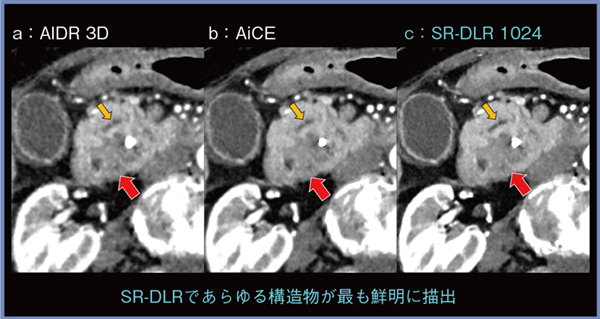

■症例提示

症例1は,83歳,女性,膵頭部がん症例で,閉塞性黄疸のため胆管ステントが留置されている。低吸収を示す膵がん(図2↑)は,AIDR 3D(a)やAiCE(b)でも診断可能であるが,SR-DLR 1024(c)にて最も鮮明に描出されおり,また,腫瘍近傍を走行する膵管(↓)や,膵臓周囲の脈管や胆囊壁など,あらゆる構造物が明瞭となっている。膵周囲の動脈のMIP画像(図3)でも,SR-DLR 1024(c)にて明らかに描出能が向上しており,3D解析を行えば高精細な手術支援ツールとしても役立つと思われる。

さらに,肝転移の視認性も良好であり,SR-DLR 1024を用いることで,正確度が高く,包括的な膵がんの画像診断が可能になると期待される。

図2 症例1:膵頭部がん(83歳,女性)

BMI 20.8kg/m2,CTDIvol 4.1mGy